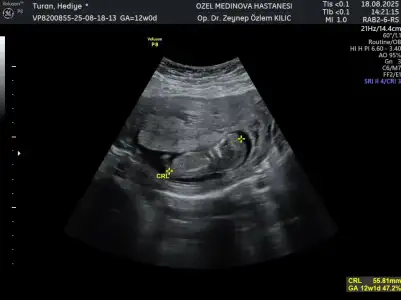

Merhaba arkadaşlar Sizce cinsiyet nedir 12 haftalık iken . İkili tarama için özele gittim doktor bir yorumda bulundu 15 haftalık kendi kendi doktoruma gittim o da bir yorumda bulundu ama ben sizin düşüncelerinizi merak ediyorum iki doktorun da kız yönünde tahmin yaptı ama kesin bir şey demediler ilk 2 fotoğraf 15 haftalık öbürü de 12